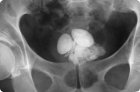

В норме моча содержит не более 5% солей, но при определенных условиях их концентрация возрастает, и тогда на основе солевых кристаллов могут образовываться конкременты – камни в мочевом пузыре. Данный процесс называется цистолитиазом, а связанные с ним патологии имеют по МКБ-10 код – N21.0-21.9.